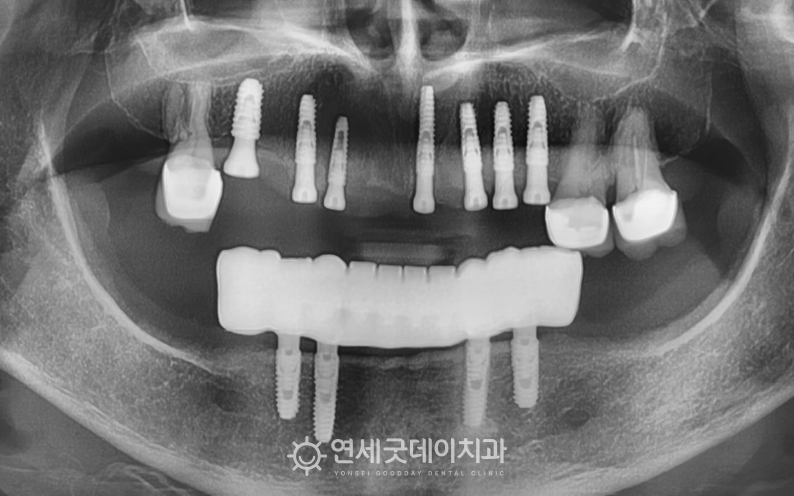

▲ 하악 All-on-X 셋팅 및 상악 임플란트 식립

(촬영시기 : 2025년 12월)

하악은 All-on-X 치료가 마무리되었습니다.

상악은 골이식과 함께 7개의 임플란트를 식립했으며

비교적 상태가 양호했던 #17,26,27은 자연치아를 유지하는 것이

더 좋다고 판단되어 살리는 방향으로 도와드렸습니다.

▲ 상악 임플란트 식립(촬영시기 : 2025년 12월)

상악의 경우, 골이식을 통해 두툼한 잇몸뼈가 형성되었으며

그 위에 식립된 임플란트가 잘 고정된 모습입니다.

하악은 맞춤형 바를 고정하여 임플란트 틀니를 연결하였고

기존 대비 심미적이면서 안정적인 고정성을 확인하였습니다.